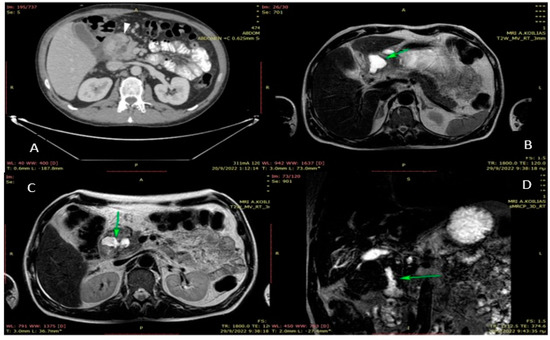

2. Case Presentation